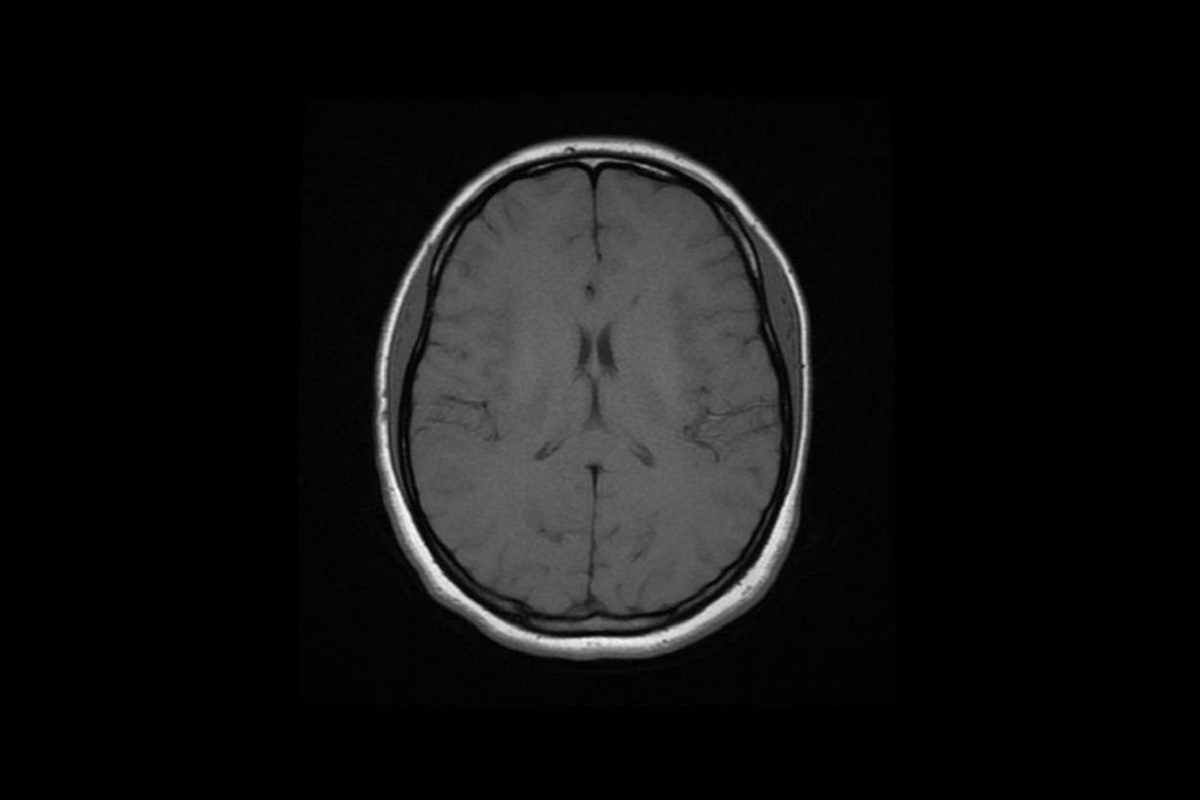

Американские врачи испытывают новый метод лечения рака мозга. В своем эксперименте они используют для борьбы с раковыми клетками вирус простуды.

Нейрохирурги Университета медицинских наук Арканзаса (UAMS) уже испытали свою методику на 63-летней пациентке, внедрив в опухоль аденовирус, который должен уничтожить раковые клетки.